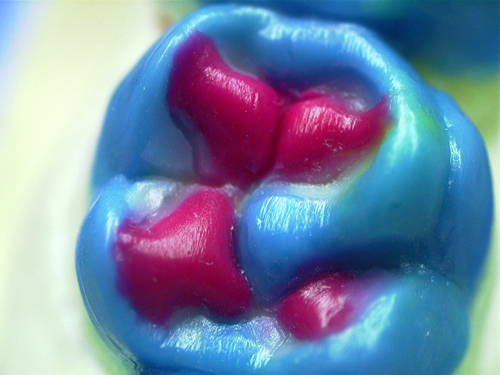

ABSTRACT El Bruxismo es una entidad patológica en la que concurren diferentes factores. Entre ellos el stress que conlleva consigo la vida moderna, constituye el Factor Predisponente sobre el que se ha abundado en innumerables tratamientos de tipo general, actuando sobre la psiquis y el comportamiento del individuo, ya sea con fármacos o bien mediante medios psicológicos. Sin embargo, como tantos desequilibrios provocados por el stress, confluyen siempre con un Factor Desencadenante, que en el caso del Bruxismo se encuentra en las desarmonías entre los componentes varios del Sistema Estomatognático. DESARROLLO Paciente varón, de 43 años, constitución atlética. A la inspección se observan desgastes oclusales que alcanzan la calidad de Facetas Parafuncionales, con dentina expuesta y empastes totalmente gastados y evidentes signos de falta de Disclusión Canina de ambos lados. Sobre dicho montaje se realiza un Encerado Progresivo de Diagnóstico, aportando en el mismo los elementos necesarios para obtener todos los principios básicos de una Oclusión Orgánica. FIG. 6 a 24 Una vez aprobado el fisiologismo de la oclusión en el articulador, se reproducen modelos de yeso con la nueva situación, y se estampa un SET UP en cada maxilar. FIG. 25/26 Procedemos entonces al tallado de las piezas correspondientes a la Guía Anterior, y rebasamos los estampados, creando en boca una nueva situación desoclusiva, que permanece en boca durante los pocos días que transcurren entre la primera y segunda visita de trabajo. FIG. 27/33 Ya abordando en esta segunda visita los sectores posteriores, tanto superiores como inferiores, tallamos siempre de manera supragingival, destacando la importancia vital de la forma obtenida en las provisionales, a las que abrimos plenamente las troneras para lograr una correcta higiene. FIG.34 a 43 FIG. 44 a 52 Efectuados los colados en oro y probados en boca, en el laboratorio se confecciona el bizcochado de la nueva Guía Anterior, la que puede o no copiarse de la Guía Anterior provisional, mediante la técnica denominada Trayectoria Funcionalmente Generada, que consiste en realizar en la platina del articulador un registro estereográfico sobre acrílico Duralay en polimerización. FIG. 57/58 Ajustados todos los detalles mediante esta técnica, se instala en boca en forma Provisional y se deja funcionando una semana o dos, al cabo de las cuales se chequean las disclusiones , los ajustes, la eficacia masticatoria, la carencia de sintomatología articular y muscular. FIG.59 a 63 PIE DE FOTO FIG.9 OBTENCIÓN DE LA GUÍA ANTERIOR FIG.10 Y 11 PITOMBOS. ALINEAC. TRIDIMENSIONAL FIG.12 PITOMBOS. DISCLUSIÓN DER. FIG.13 PITOMBOS. DISCLUSIÓN IZQ. FIG.14 WILSON INF. FIG.15 WILSON SUP. FIG.16 BOCA DE PEZ INF. FIG.17 BOCA DE PEZ SUP. FIG.18 VISTA OCLUSAL FIG.19 O.R.C. FIG.20 DISCLUSIÓN DERECHA FIG.21 CRESTAS TRIANG. INT. FIG.22 CRESTAS TRIANG. INT. FIG.23 CRESTAS TRIANG. INT. FIG 24 CRESTAS TRIANG. INT. FIG.59 DISCLUSIÓN IZQ. FIG.60 DISCLUSION IZQ. FIG.61 DISCLUSIÓN DER. FIG.62 DISCLUSION DER. FIG. 63 AJUSTE PERIFÉRICO